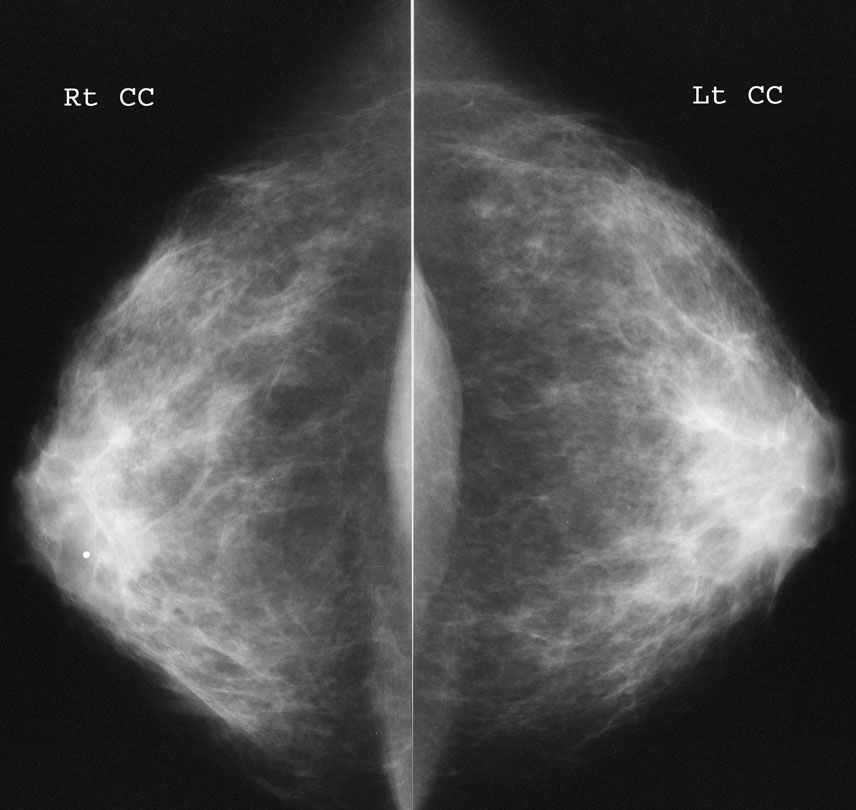

Что такое маммография: важность, процесс и результаты